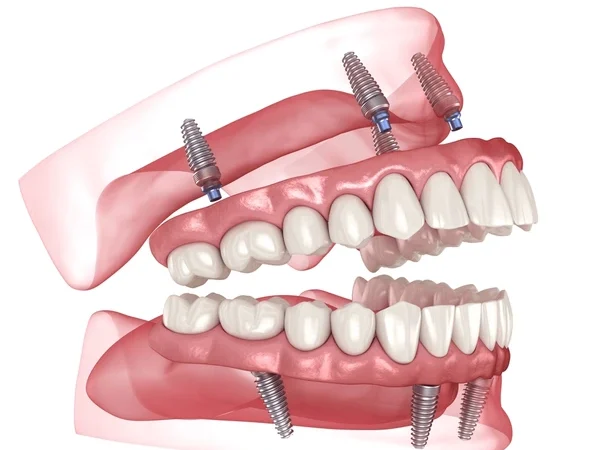

Cấy ghép implant toàn hàm là một quy trình phức tạp nhưng mang lại hiệu quả lâu dài trong việc phục hồi chức năng ăn nhai và thẩm mỹ. Thời gian thực hiện có thể khác nhau tùy theo phương pháp, số lượng trụ và tình trạng xương hàm của từng người. Bài viết dưới đây sẽ giúp bạn hình dung rõ hơn.

| Implant truyền thống | 6 – 10 trụ | 2 – 4 giờ | Khoan – đặt trụ – khâu từng vị trí |

| Implant All-on-4/6 | 4 – 6 trụ | 1 – 2 giờ | Đặt trụ theo góc nghiêng, ít xâm lấn hơn |